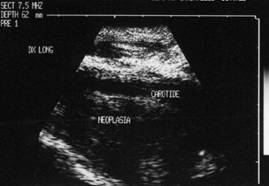

Lob drept, proiectie trasversala si longitudinala

Barbat de 65 ani. Recidiva voluminoasa

laterocervical dreapta dupa un neoplasm anaplazic cu celule fuzate; tratament -

chimioterapie si radioterapia. Carotida dreapta inglobata si infiltrata